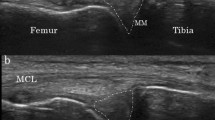

A high-resolution dataset was acquired using a Vantage Galan 3 Tesla Canon® MRI machine with a 71 cm bore to assess the kinematics of the menisci and for validation purposes. A Proton Density (PD) weighted MRI sequence was used to visualize the menisci and the bony contours. For the dedicated knee scans, a pixel size of 0.3571 mm to 0.3571 mm and a slice thickness of 1.5 mm was obtained. The coronal overview scans had a pixel size of 0.7308 mm to 0.7308 mm and a slice thickness of 3 mm.

For every subject and dedicated scan, manual segmentation of both the medial and lateral meniscus was performed using the Mimics® software16. The segmentation process involved meticulous determination of the meniscal edges, aided by the built-in Livewire function. This interactive tool assisted in accurately tracing the contours of the menisci. Segmentation masks were subsequently converted into three-dimensional volumes of the medial and lateral menisci, providing a comprehensive representation of their anatomical structures.